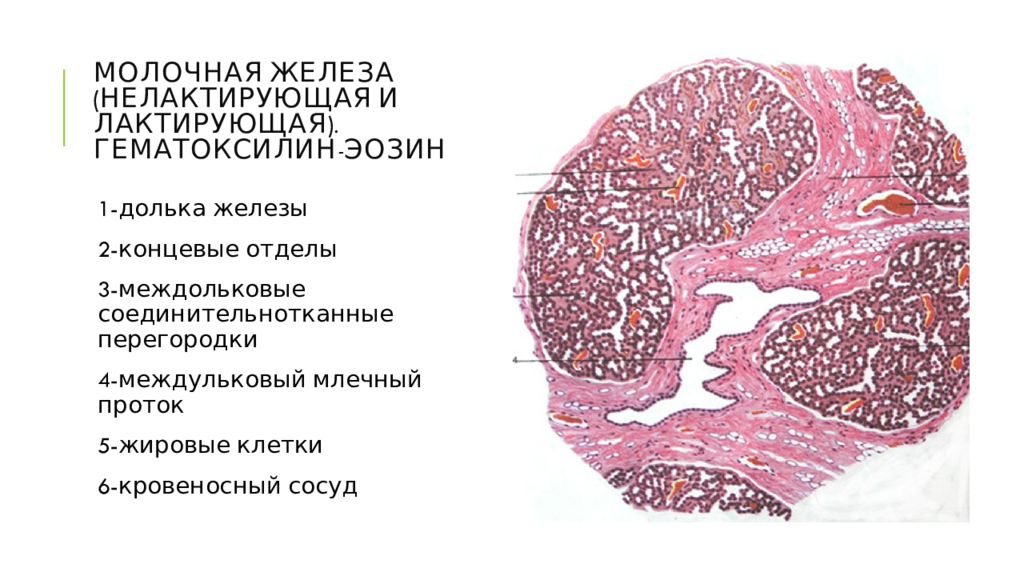

Исследование: микропрепарат молочной железы в медицине

Раздел: Снимки-откровения